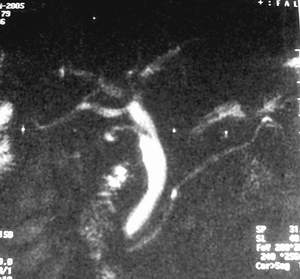

患者,男,57岁,梗阻性黄疸10余天。

这个病例胰头无明显增大,胆总管扩张明显而肝内胆管扩张更不明显,病程较短,

注意到十二指肠乳头明显突出,但尚光滑。分析以下可能性:

1、十二指肠乳头本身的病变,如乳头炎症;

2、急性乳头水肿,胆总管下端结石排石后乳头水肿;

3、壶腹部胆总管下端肿瘤累及十二指肠乳头。

十二指肠乳头粘膜慢性非特异性炎症